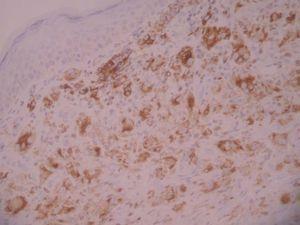

A las 38 semanas del tratamiento la paciente presentó varias lesiones papulosas semiesféricas eritemato-amarillentas en mejilla derecha (zona preauricular) de pocos milímetros de diámetro, muy bien definidas y tacto sólido (fig. 4). Se tomó una de las lesiones para estudio histopatológico, que mostró un infiltrado difuso en dermis papilar y reticular superficial, constituido en su mayor parte por histiocitos de citoplasma amplio, basófilo, con xantomización ocasional (fig. 5). Se observaban algunos linfocitos y eosinófilos entremezclados. El estudio inmunohistoquímico de estas células mostró un perfil macrofágico CD68+ , S-100 y CD1a (fig. 6). Por todo ello, se llegó al diagnóstico de xantogranuloma juvenil. Durante los meses siguientes al final del tratamiento de la HCL no se observaron lesiones de dicha enfermedad en la piel ni a otros niveles, pero siguieron apareciendo pequeñas pápulas compatibles con XGJ en cara, tronco y miembros.

Fig. 6.—Tinción positiva con CD68.